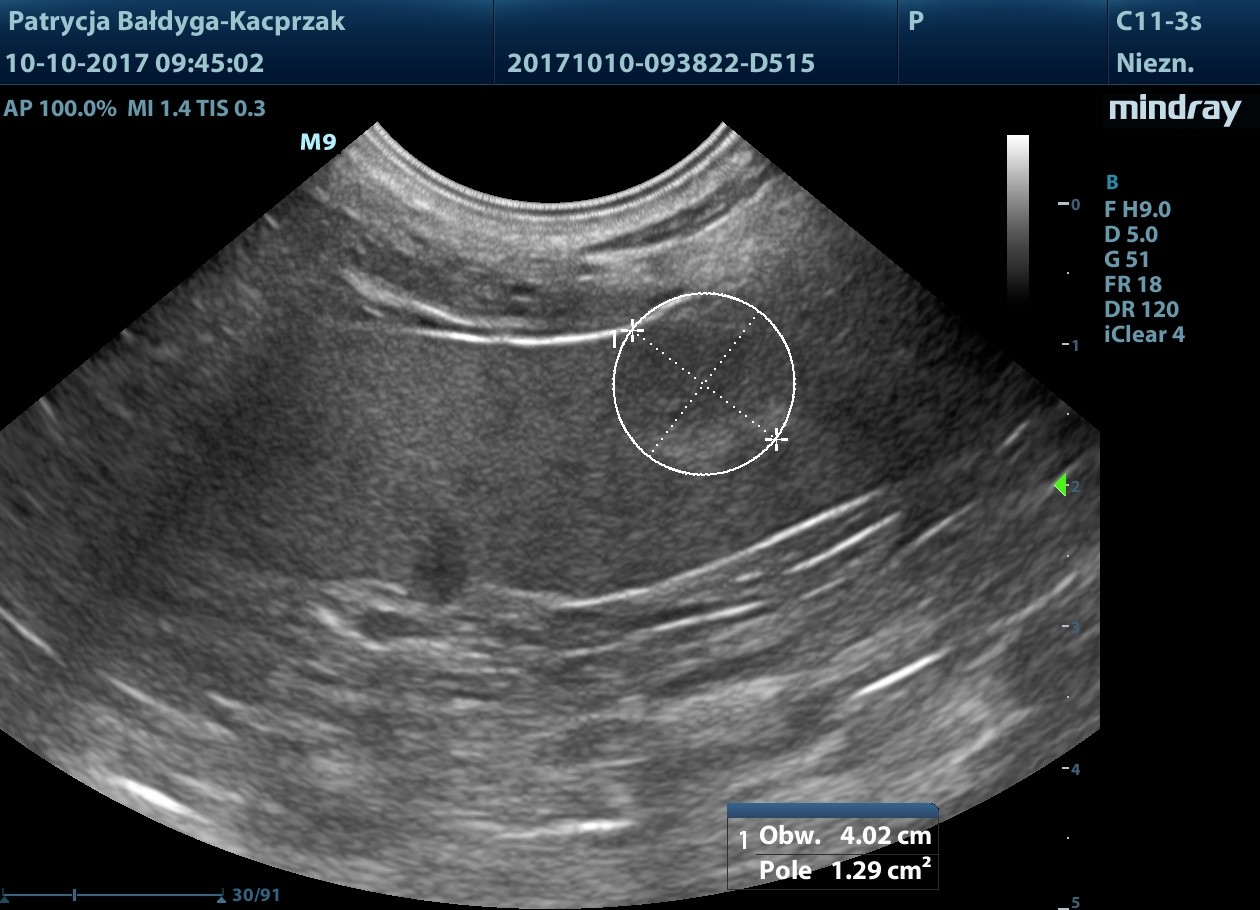

Śledziona niepowiększona, miąższ nieco niejednorodny zobecnością zawnękowo, przyściennie zmiany ogniskowej

słabo odgraniczonej, nieco hipoechogennej w centrum, hiper obwodowo, wielk. ok. 1,2 cm, mniejsza widoczna przedwnękowo, od pow. trzewnej, podtorebkowo śr. ok. 6-8 mm

niejednorodnie hipoechogenna, nieregularna, zmiany nie modulują brzegu narządu, bez cech patognomicznych.